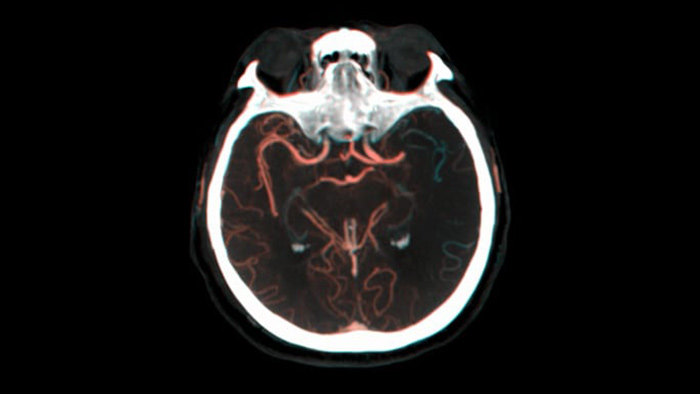

ein Schädel mit roten Adern

SmartCT Roadmap bietet anatomische Referenzbilder zur Unterstützung einer präzisen Navigation von Führungsdrähten, Kathetern und Instrumenten zum Gerinnsel.